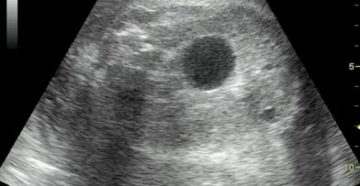

Что может на узи показать затемнение в почках Ультразвуковая диагностика почек является максимально информативной при…